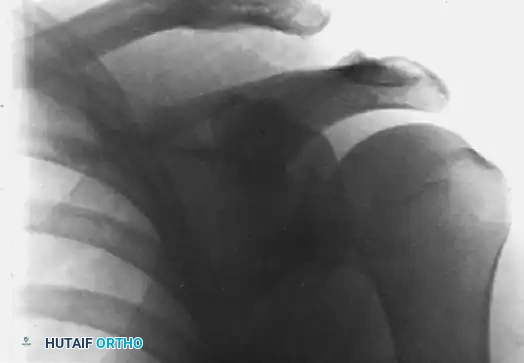

FIGURE 1: Stewart technique for acute dislocation of the acromioclavicular joint. (A) Radiograph demonstrating the acute injury with superior displacement of the distal clavicle.